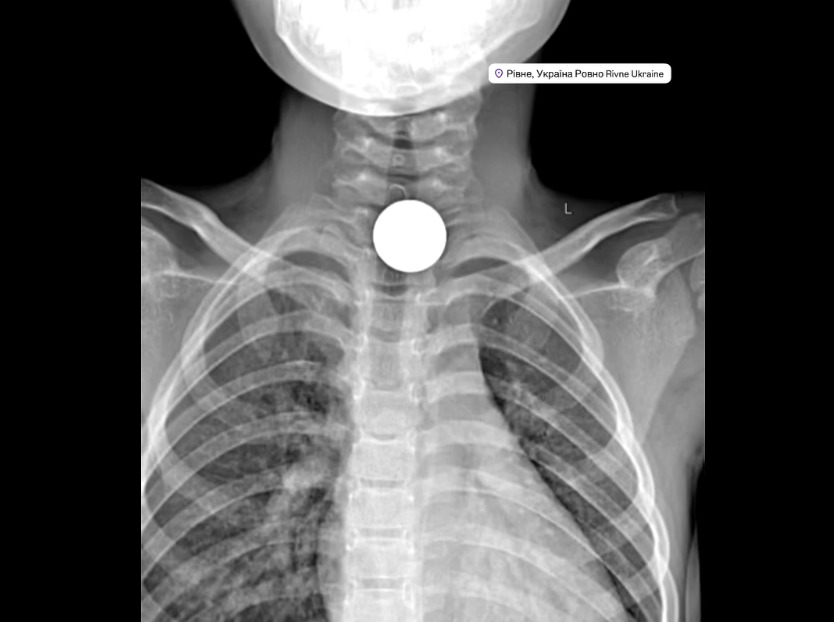

Під час обстеження рентген-знімок показав, що монета перебувала у верхньому відділі стравоходу, в ділянці входу до нього. Такий стан є потенційно небезпечним і потребує негайного медичного втручання.